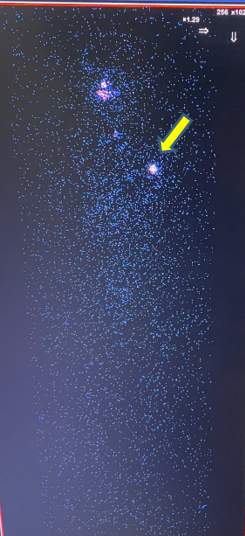

- Chụp xạ hình toàn thân với I-131 liều 5 mCi:

Tại vị trí tuyến giáp tập trung hoạt độ phóng xạ ngang mức phông.

Trên xạ hình toàn thân có 1 điểm bắt xạ bất thường tại vị trí vùng ngực trái.

Hình 4. Hình ảnh xạ hình toàn thân với I-131.